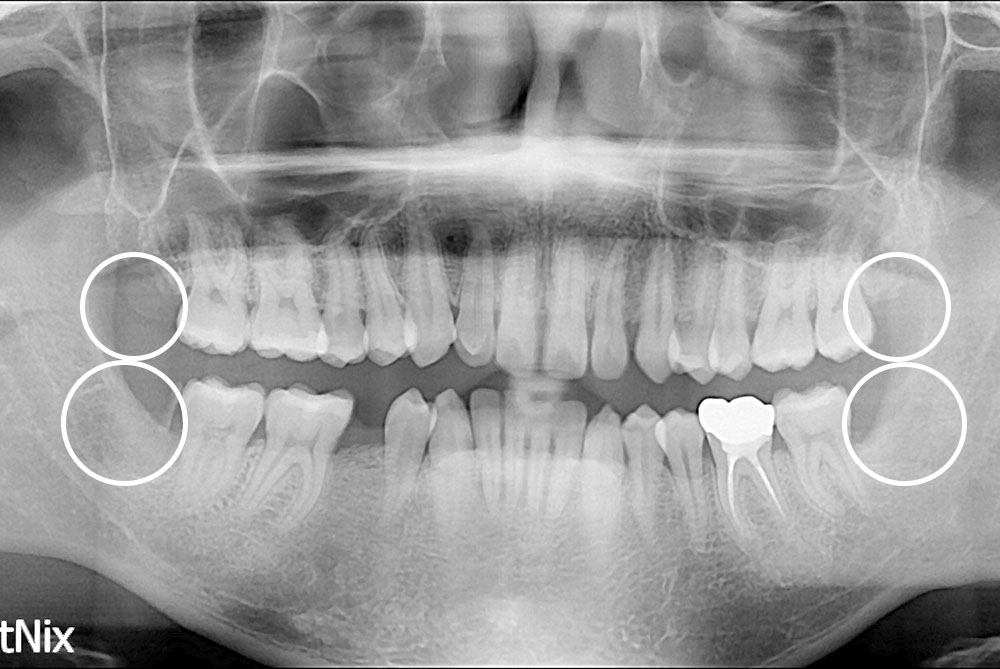

[사랑니] 매복 사랑니 발치

치료후 : 2019-04-15

세종치과는 구강악안면외과학 박사이신 원장님이 발치하는 치과입니다.